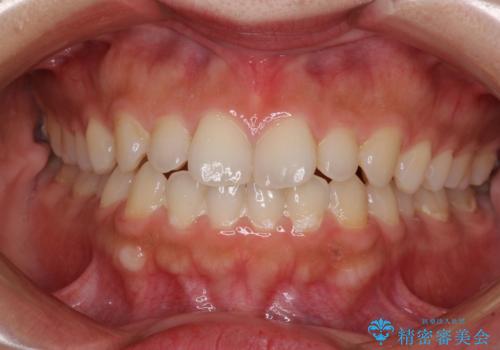

著しい八重歯が気になる インビザラインでの矯正治療